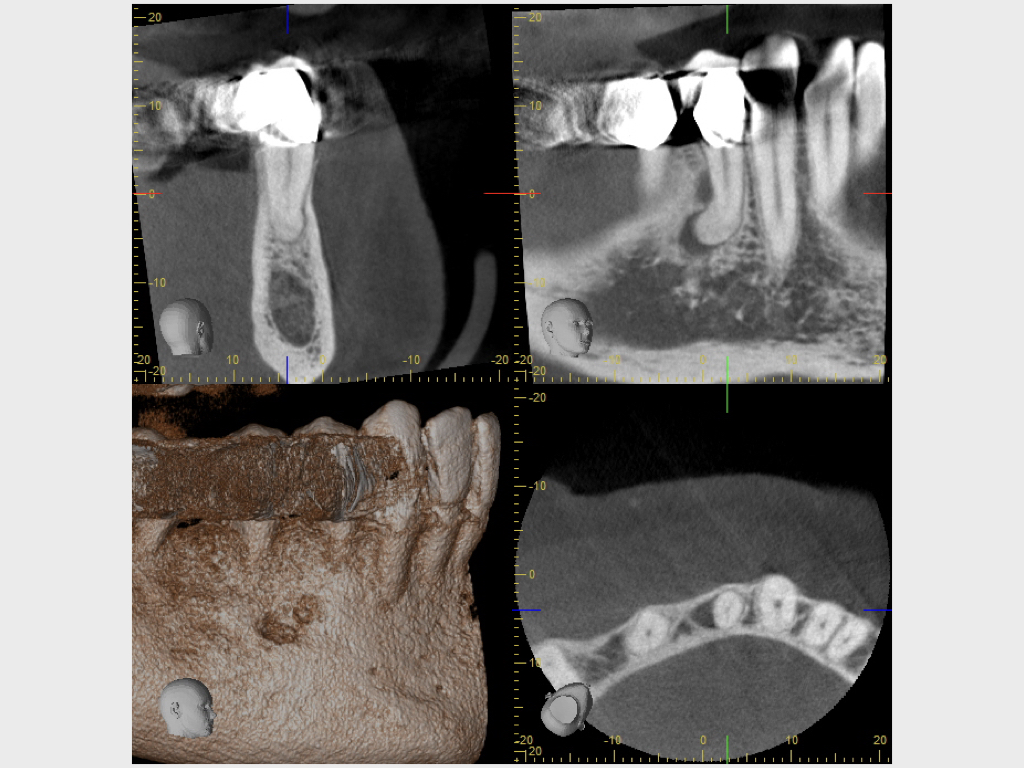

8088.003 Veröffentlicht 16. Februar 2021 am 1024 × 768 in Recall eines Misserfolges, bzw. Glücksfalles